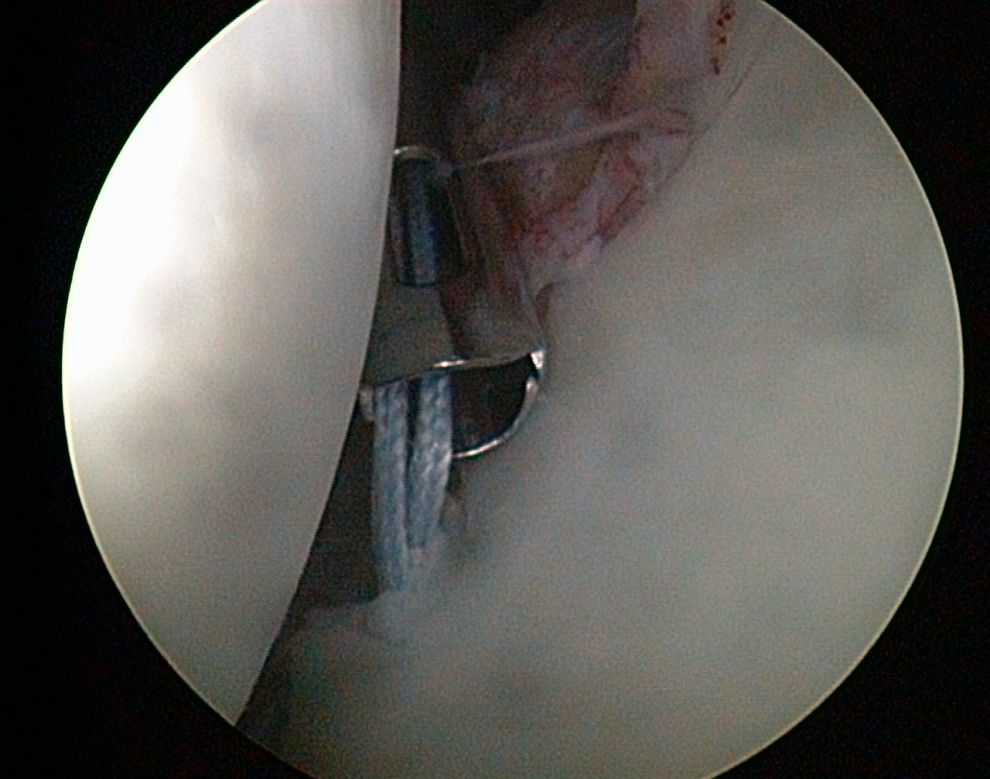

HD-Bilder aus dem Schulter- und Kniegelenk

- zielgenaue Behandlung (gute Sicht dank stark vergrößerter Gelenkdarstellung über HD-Monitor)

Schultergelenk

- Naht beim Sehnenriss der Rotatorenmanschette

- Annähen der Schulterpfannenlippe nach Riss infolge von Verrenkungen

- Stabilisierung des Schultergelenkes

- Entfernung von Schulterkalk